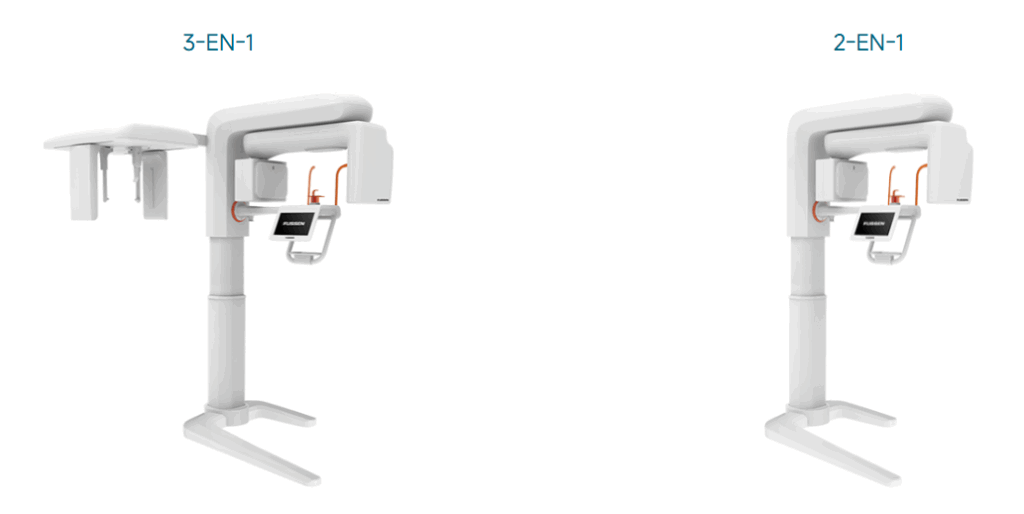

D50

2 CHAMPS DE VISION